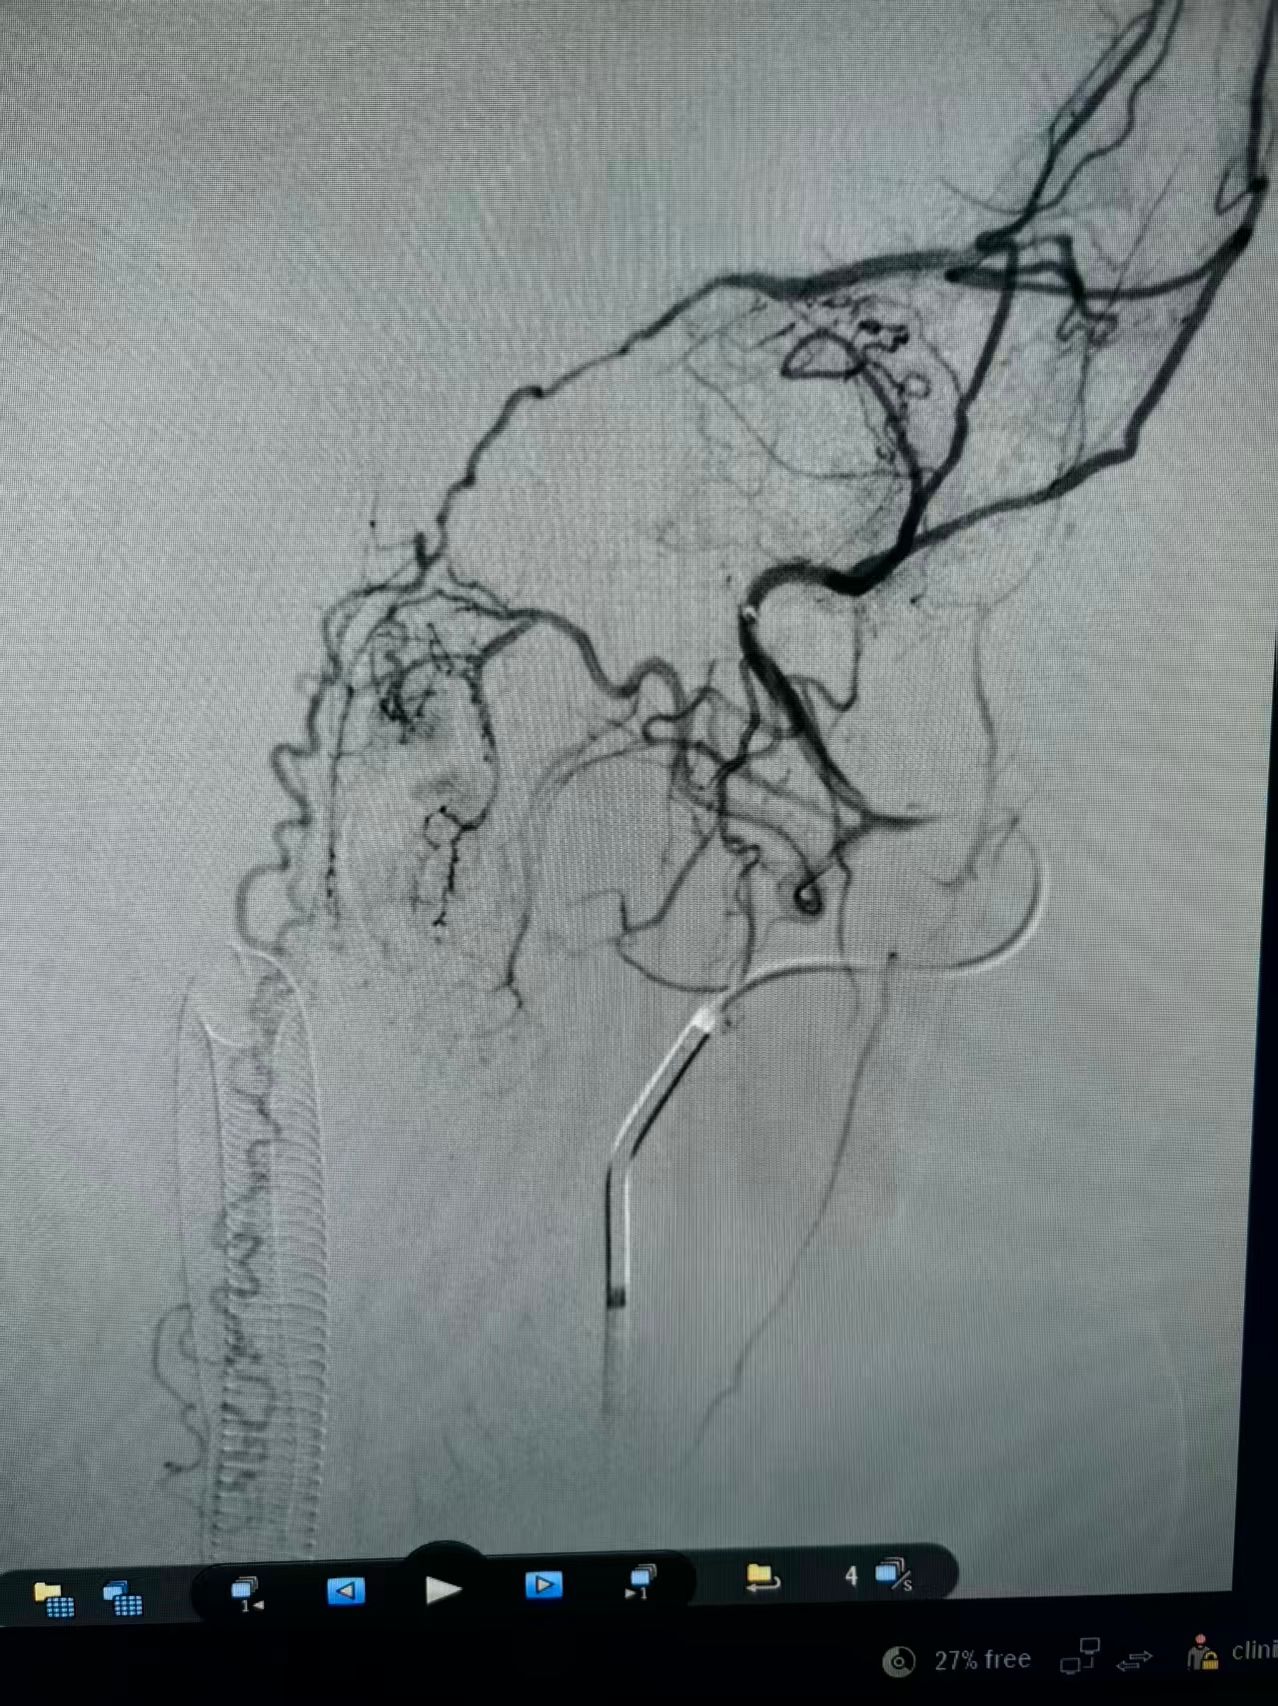

团队结合患者病史、影像学检查以及使用激素后加重的特征,讨论后认为动静脉瘘的可能性较大。但全脊髓造影并未发现硬脊膜动静脉瘘,那么,这个瘘会不会在颅内,只是朝脊髓引流了。根据这个猜测,许刚副主任医师团队为患者进行了全脑血管造影,初步的血管造影并未发现明显病灶。团队并未轻易放弃,又对可疑的各分支血管进行了超选择性造影。最终发现了该患者为脑膜中动脉及枕动脉脑膜支供血的一个非常细小的瘘口。该瘘位于岩骨脊,向下朝脊髓引流,不仔细研究很可能发现不了。

术前脑膜中超选正位